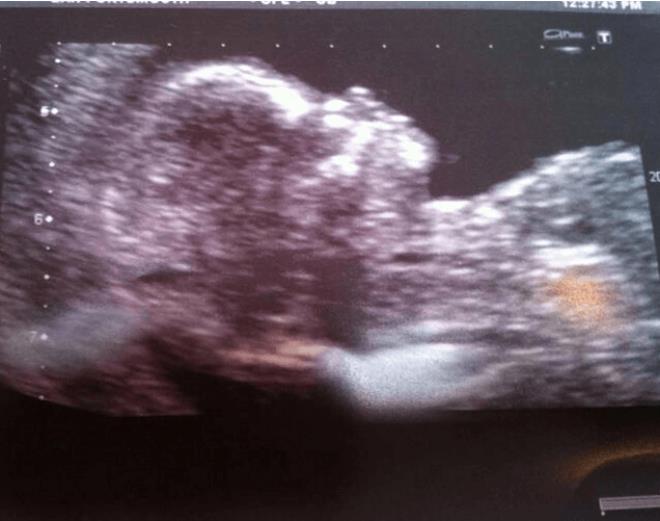

Hamile kaldığı zamandan bahseden Nicole şunları söyledi: "Bir gün mide ekşimesi ve ağrıyan göğüslerle baş başa kaldığımda dayanılmaz derecede acı çekiyordum. O sırada yakın bir arkadaşım hamile olabileceğimi söyledi. Güldüm ve hala bakire olduğum ve hiçbir zaman nüfuz edici seks yapmadığım için hiçbir yolu olmadığını söyledim. Ancak tüm bunlara rağmen hamilelik testi yaptım ve pozitif çıktı. İnanamadım, çok şok olmuştum ve kafam karışmıştı."

Genç kadına bazı tıp uzmanları inanmakta güçlük çekse de nadiren de olsa, cinsel aktivitenin vajinal bölgeye sıvı vermesi durumunda penetratif ilişki olmadan hamile kalmanın mümkün olduğu doğrulandı.